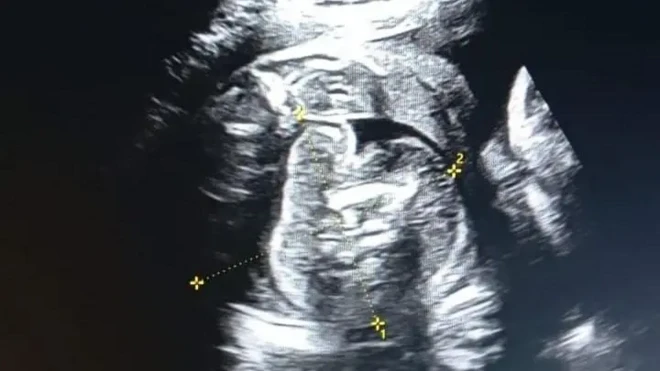

مگر اینا پاؤلا کے معاملے میں ایسا نہیں۔ اس تحقیق کے دوران ہی وہ دوبارہ حاملہ ہوئیں اور ایک صحت مند بچے کو جنم دیا۔

جینیاتی تجزیے سے پتہ چلا کہ بچے کا ڈی این اے توقع کے مطابق ہے یعنی آدھے کروموسوم اس کی ماں اور آدھے اس کے والد سے ہیں جبکہ بچے کے انکل سے کوئی کروموسوم نہیں۔

پروفیسر میکیل کہتے ہیں کہ ’اینا پاؤلا کے انڈے میں ان کا جینیاتی مواد تھا اور ان میں گردش کرنے والے خون نے مداخلت نہیں کی۔‘